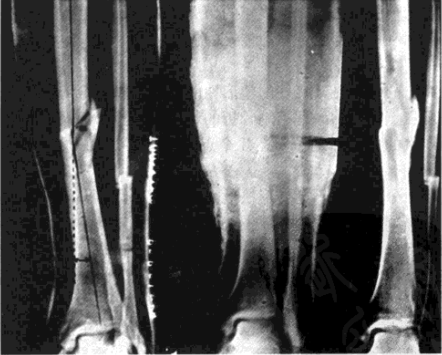

在石膏管型固定中,通过楔形切开矫正骨折残存的成角畸形(图5-2, 5-3)仍是行之有效的方法。某些开放性骨关节损伤,利用石膏管型固定,局部开窗观察或处理创面也有其可取之处(见图4)。

△ 图4 在石膏固定中,观察伤口局部皮肤变化